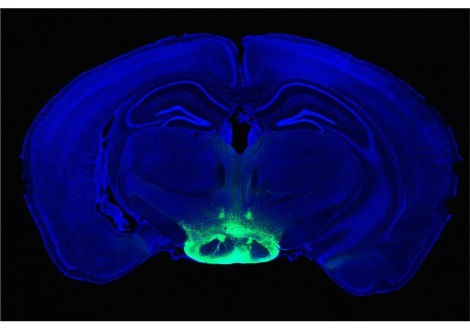

تنبأ الباحثون في هذه الدراسة عمر عقول عيّنة الدراسة عن طريق استخدام تقنيّة توظّف الذكاء الصناعي لتحليل المعلومات عن طريق مسح الدماغ حسب ما تقوله الدراسة المنشورة في الخامس والعشرين من نيسان عام 2017 في مجلّة "الطبّ النفسي الجزيئي" Molecular Psychiatry.

طوّرت هذه التقنية في عام 2010 وتضمّنت قياس حجم دماغ الشخص وفحص كميّة المادة البيضاء والرمادية فيه حسب ما تقوله الدراسة. استخدم الباحثون برنامج حاسوبي "مدرّب" ليتنبّاً بأعمار 2000 شخص تتراوح أعمارهم ما بين ال 18 وال 90 عاماً عن طريق مسوحات أدمغة هؤلاء الأشخاص.

تمّ اختبار التقنيّة بعد ذلك على مجموعة مكوّنة من أكثر من 650 شخص ممن تبلغ أعمارهم 81 عاماً والذين سبق وكانوا جزءاً من دراسة اسكتلندية طويلة المدى تدعى "فوج ولادة لوثيان لعام 1936" والذين تمّ فحص أدمغتهم سابقاً في عمر 73 وكانوا قد مرّوا في اختبارات طبيّة وإدراكيّة من قبل.